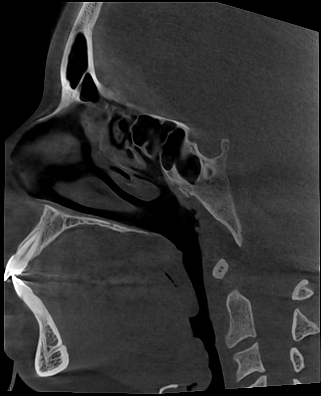

- FOV grande → senos paranasales (13cm x 16cm) o cráneo completo (23cm x 26cm)

- ATM o senos maxilares: FOV específico según la región